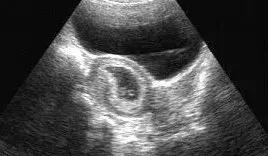

B超就是利用超声波了解体内结构的一种观察仪器。原理说白了很简单,就是发射超声波,超声波也是声音的一种,具有穿透能力,并且和所有的声音一样,遇到屏障会产生回声,不同的屏障回声的方式也不同,于是利用电脑收集这些回声,转化为相应的图像在屏幕上显示出来,起到观察内部脏器等作用。

彩超具有组织谐波成像功能,可以明显降低因肥胖、气体和其它伪像干扰,提高图像清晰度。因此,彩超检查能够更早期地发现病变,并能够更加准确地对病变进行鉴别诊断,明显提高诊断的准确率,而B超检查的漏诊率和误诊率则明显高于彩超。